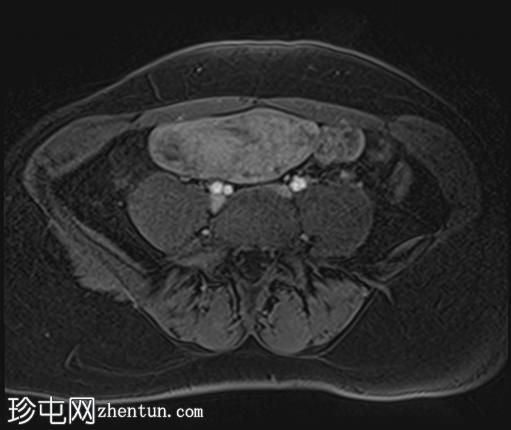

轴位T1加权像

增强脂肪抑制像

盆腔内可见多个边界清晰的肿块:

其中一个位于子宫上方,T2加权像呈中等信号,中心区域呈高信号,增强T1脂肪抑制像未见强化。右侧卵巢增大,增厚的血管蒂扭曲,未见强化,轴位和矢状位T2加权像均显示清晰。

另一个位于子宫后窝,T2加权像呈中等信号,增强扫描显示明显强化。

轻度腹腔积液

2个月前进行的MRI检查显示双侧卵巢肿块均有强化,右侧卵巢肿块未见扭转。